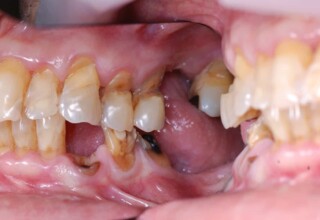

Εκτεταμένη αποκατάσταση με στεφάνες(θήκες) σχεδόν σε όλα τα δόντια λόγω εκτεταμένων αποτριβών, παλαιών αποκαταστάσεων, οπισθίων απονευρώσεων και αισθητικών προβλημάτων. Ο ασθενής(60 ετών) παρουσίαζε έντονο βρυγμό (τρίξιμο δοντιών) που δεν είχε αντιμετωπίσει ποτέ, με αποτέλεσμα μεγάλες αποτριβές που απειλούσαν την ακεραιότητα των οπισθίων δοντιών. Οι ανασυστάσεις(σφραγίσματα) των δοντιών έγιναν κυρίως με συγκολλούμενα ρητινώδη υλικά και τρεις χυτούς άξονες ψευδοκολοβώματα. Τοποθετήθηκαν προσωρινές στεφάνες όπου εκτιμήθηκε το επιθυμητό μέγεθος, το σχήμα και η θέση των δοντιών πριν κατασκευαστούν οι τελικές μόνιμες στεφάνες.